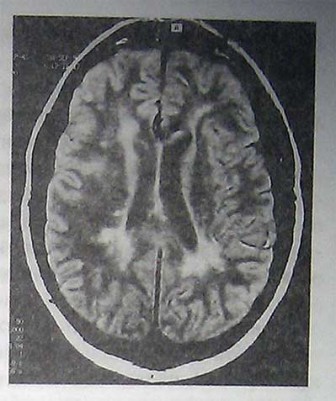

- Магнитно-резонансная томография (МРТ) может выявить очаги поражения в головном и спинном мозге. Чтобы выявить повреждения, находящиеся в активной фазе, в кровь вводится специальный контрастный материал.

Благодаря высокой чувствительности и неинвазивности МРТ стал наиболее полезным тестом, подтверждающим диагноз PC. Основной недостаток МРТ— отсутствие специфичности. К сожалению, рассеянные очаги в субкортикальном и перивентрикулярном белом веществе могут выявляться при множестве других заболеваний, например, при сосудистой патологии, васкулитах, мигрени, а в ряде случаев и у лиц, которых можно счесть практически здоровыми. По этой причине не следует полностью полагаться на данные МРТ при диагностике PC, иначе это приведет к его гипердиагностике